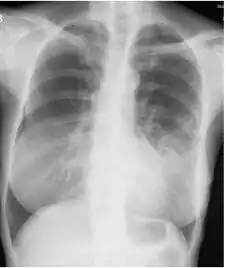

Image indicate bronchodilation, centrilobular granular shadow, and consolidation -

Chest radiograph -